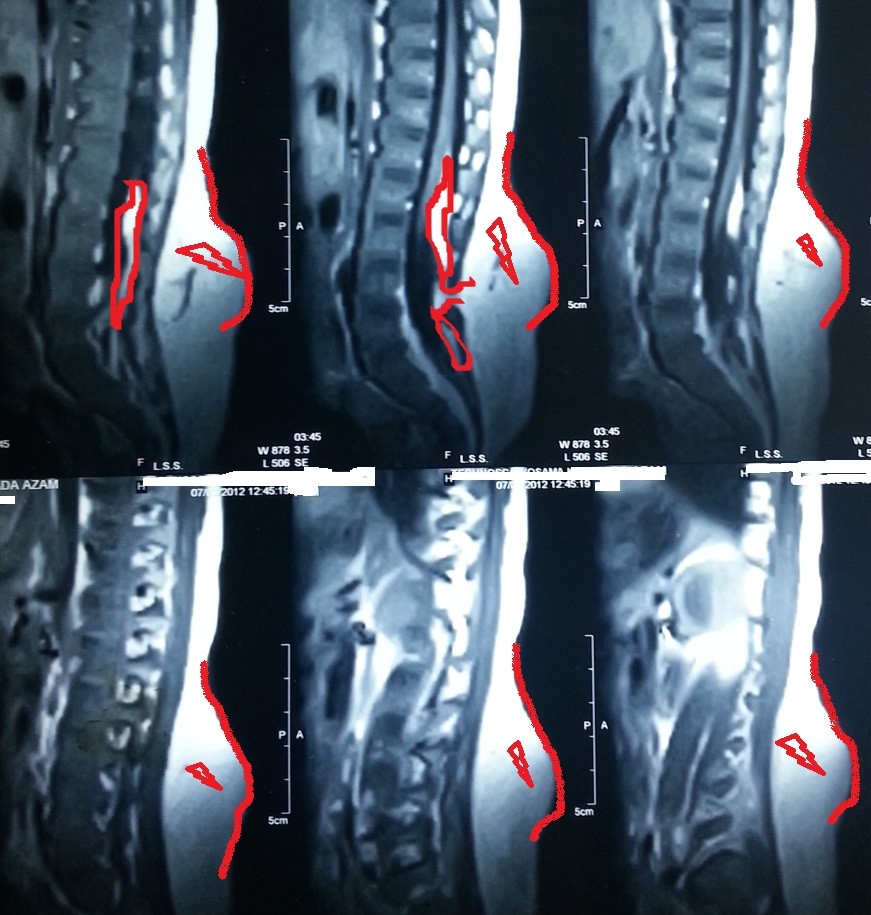

congenital fatty tumor of the spinal cord versus the lumbar vertebrae of a four-year-old girl